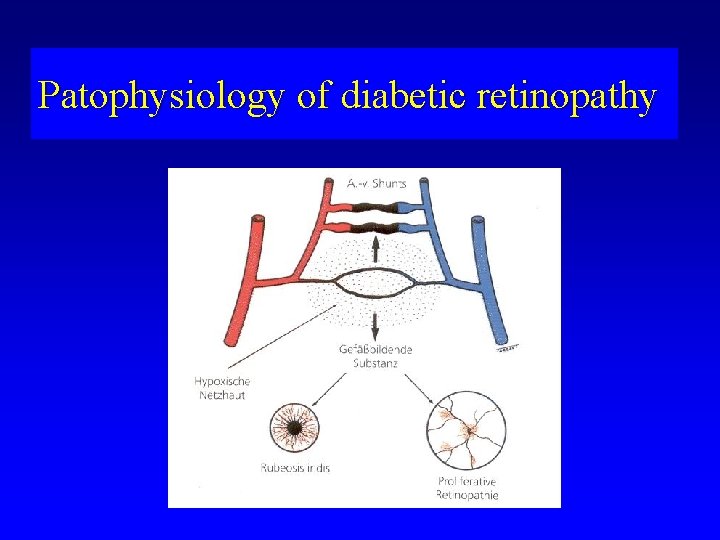

Patophysiology of diabetic retinopathy

Patophysiology of diabetic retinopathy • Microangiopathy • Lost of endothelial cells and pericites • Thickening of basal membrane of retinal capillaries (glycoproteins) • Failure of outer and inner blood retinal barrier

Patophysiology of diabetic retinopathy

Patophysiology of diabetic retinopathy

Patophysiology of diabetic retinopathy